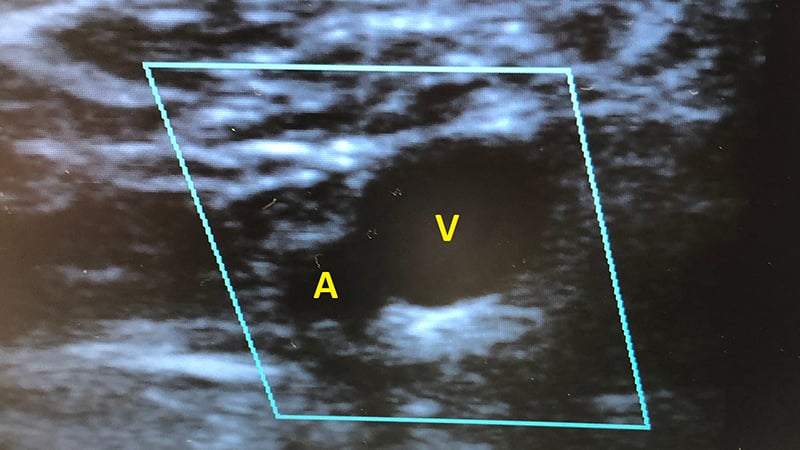

Septic arthritis is a rheumatologic emergency, which may lead to permanent joint damage and a mortality rate of 10-15%. If left untreated, non-gonococcal septic arthritis can destroy articular cartila